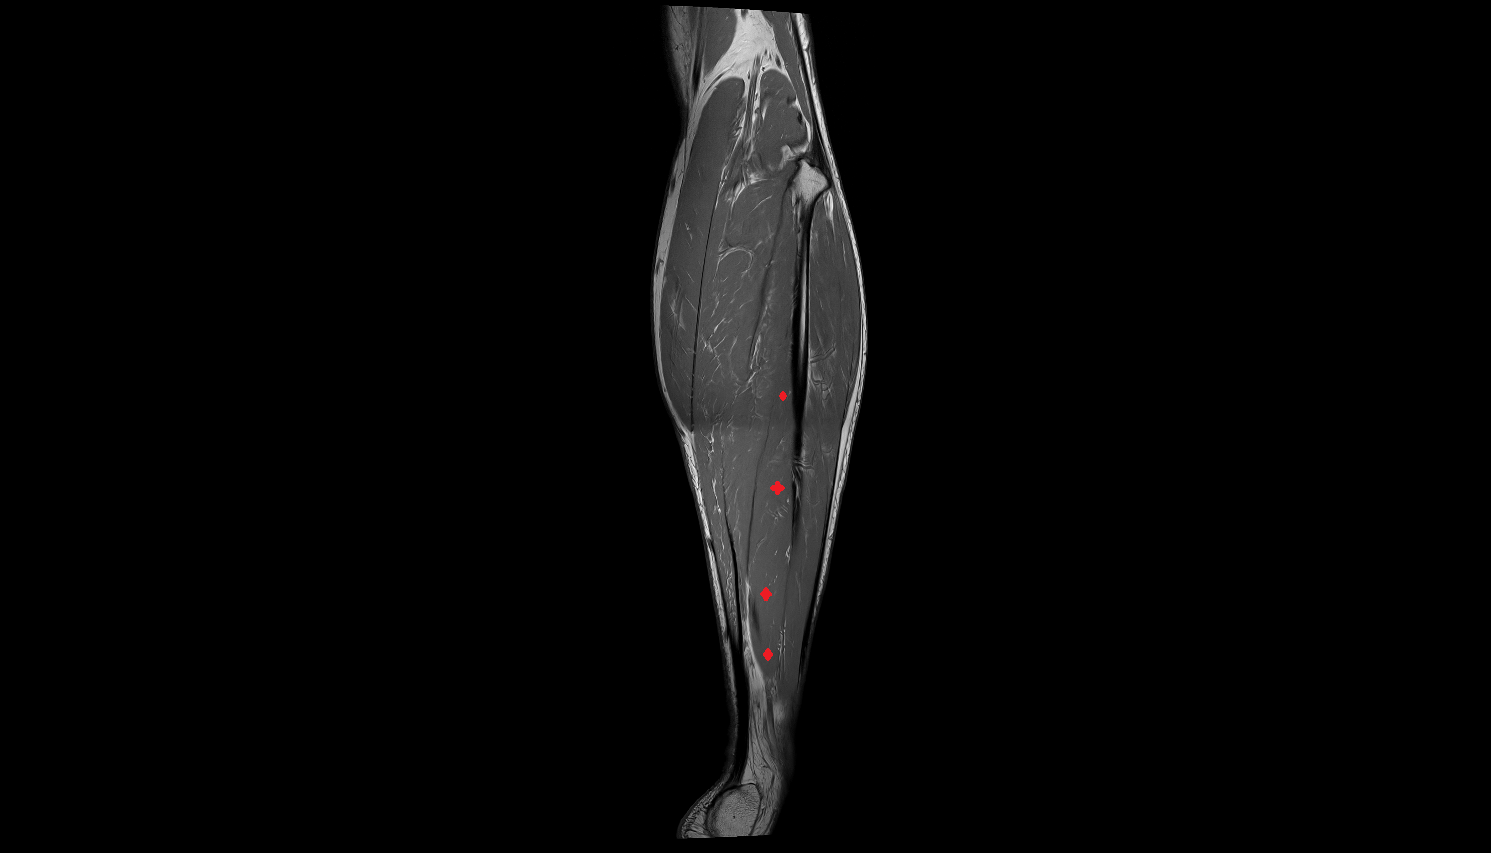

- Biceps femoris muscle (Long head)

- Semitendinosus muscle

- Semimembranosus muscle

- Plantaris muscle

- Lateral head of gastrocnemius muscle

- Medial head of gastrocnemius muscle

- Gastrocnemius muscle

- Popliteus muscle

- Soleus muscle